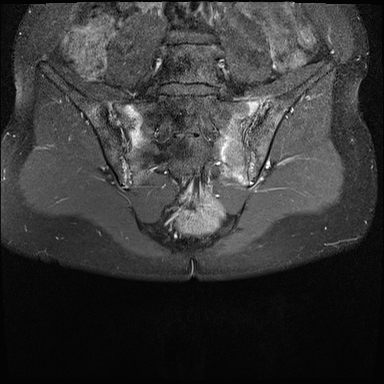

MRI

MRI chuỗi xung T1W sau tiêm thuốc tương phản từ của cùng bệnh nhân cho thấy bờ khớp cùng chậu không đều do bào mòn.

Có ngấm thuốc ở xương dưới sụn và phù nề tủy xương.

Không có tràn dịch khớp.

Thuốc tương phản từ tiêm tĩnh mạch không nhất thiết phải sử dụng để chẩn đoán viêm khớp cùng chậu.

Cuộn qua các hình ảnh MRI và so sánh với các dấu hiệu trên X-quang (hình ảnh cuối cùng).